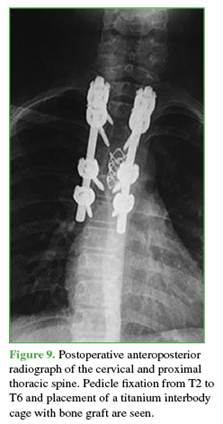

The first surgical stage was performed within 24 hours and consisted of spinal canal decompression by resection of the T4 posterior arch, followed by a costotransversectomy corpectomy using an eggshell technique to preserve the cortical rim.14 The spine was stabilized with pedicle fixation from T2 to T6.

Within the next 48 hours, angiography and embolization of the tumor’s vascular pedicle were performed.

In the second surgical stage, a titanium spacer filled  with autologous bone graft  was placed (Figure 9).